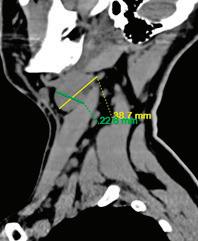

подготовка на пациента за кардиохирургична оперативна интервенция в обем 3 аорто-коронарни байпаса. От проведената КТ се установява хетероденсна формация на ниво II шиен лимфен колектор, с размери 13/18 мм. От анамнезата няма данни за болка, дисфагия, диспнея или дисфония. При наблюдение в следоперативния период се отчита постепенно нарастване на размера на формацията.

Поради динамика в локалния статус пациентът се насочва за консултация и последващо лечение в УНГ клиника, където от проведените образни изследвания (КТ, УЗД) се на -

блюдава хетероденсна мекотъканна формация с размери 25/28 мм, наличие на кистични

зони в обема й и лифмни възли по съседство.

След ексцизионна биопсия, хистологията до -

казва масивна метастаза от умерено диференциран плоскоклетъчен карцином. Насоченото

чен източник.

Случай 2: Метастатична шийна формация при тироиден карцином

месеца.

ласт от специалист ендокринолог, където е визуализиран суспектен

огнищ-

ни промени. При ТАБ – без данни за малигнитет. Пациентката се

мация, разположена пред а. каротис комунис декстра, със съмнение

тумор и значението на повторното образно изследване след хистологична диагноза.